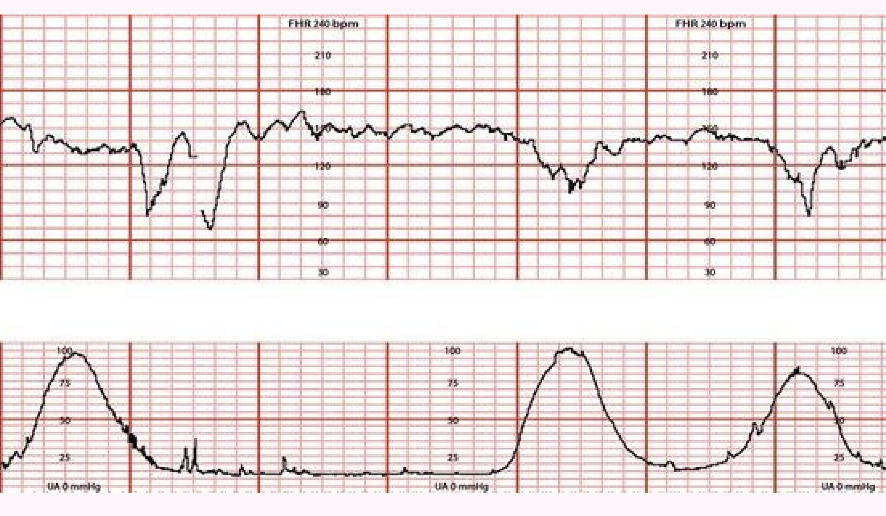

Variable: Cord compression; abrupt decrease.

If you notice this CHANGE THE POSITION!

Early: Head compression; gradual decrease/return, symmetrical, peaks with contraction.

Late: Placental insufficiency; gradual decrease/return, occurs after peak of contraction.

Category II (Indeterminate): Characteristics not Category I or III ; may include baseline heart rate between bpm with decreased variability, variable decelerations that are intermittent, and/or transient late decelerations.

Category III (Abnormal): Absent variability with recurrent late or variable decelerations or bradycardia; or sinusoidal pattern.